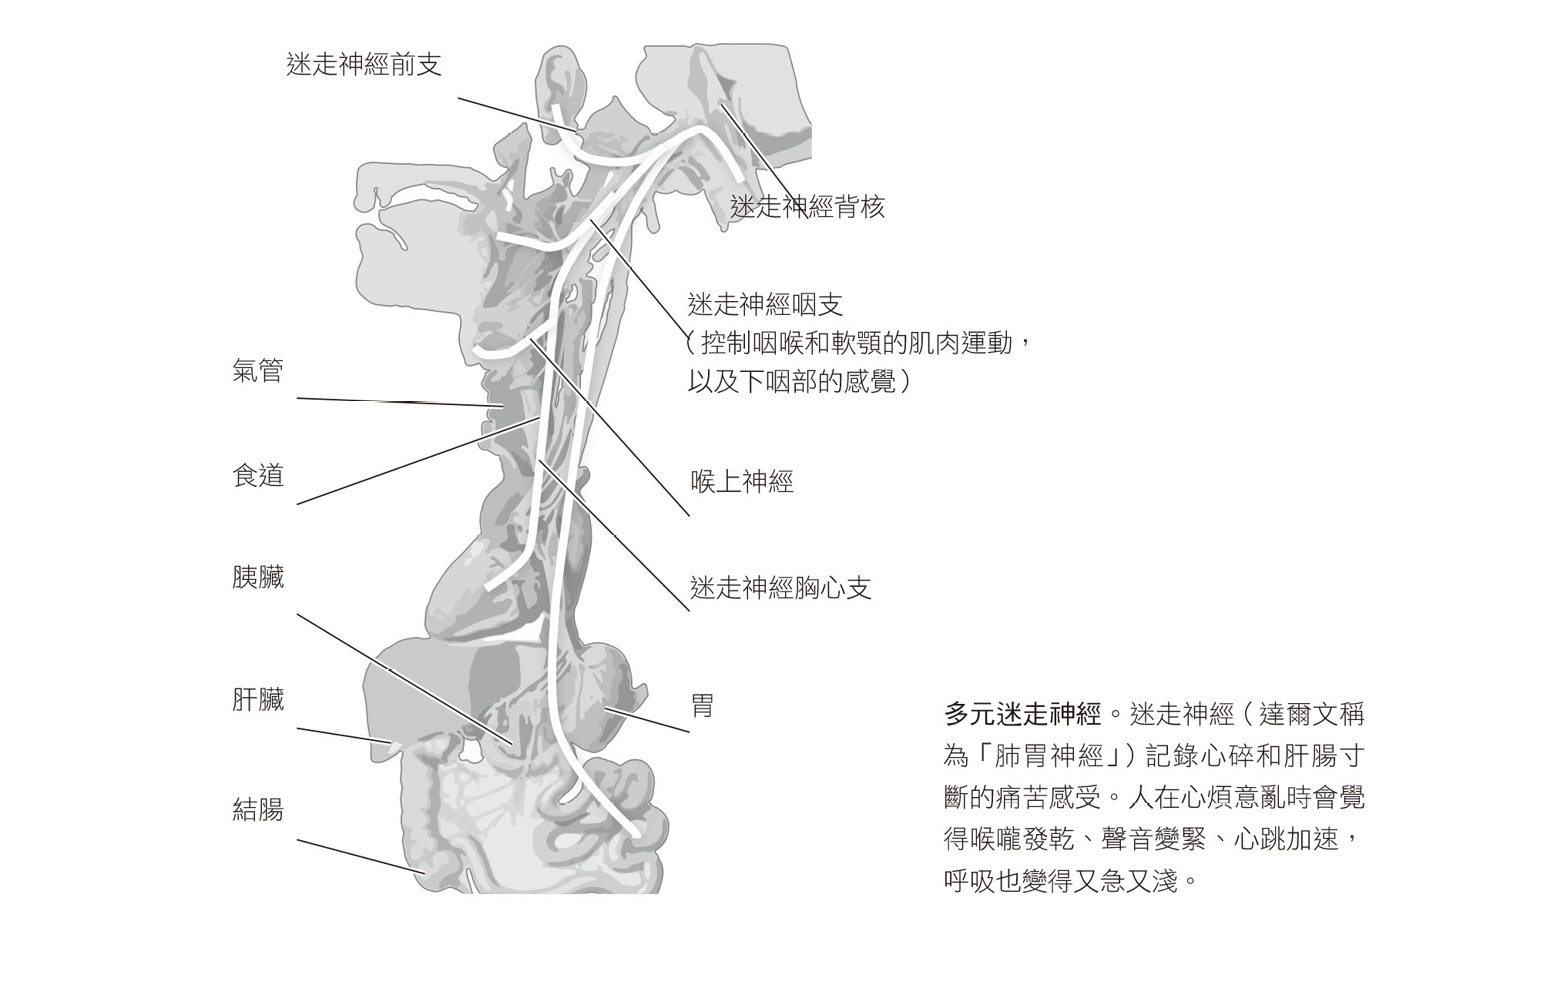

在書中,達爾文也提到我們至今仍在探索的身體—大腦連結。強烈情緒不僅涉及腦部,還牽連腸胃和心臟,他寫道:「心臟、腸胃以及大腦透過『肺胃』神經密切相連,這是人類和動物進行情緒表達與管理時最重要的神經。大腦極度活化會立刻影響內臟的狀態,因此在情緒激動時,大腦與內臟這兩種身體最重要的器官之間會有許多交互作用和反應。」4

我第一次唸到這段內容時非常興奮,於是又重讀了一次。無庸置疑,我們所經歷過最足以摧毀一個人的痛苦情緒,莫過於肝腸寸斷與心碎,如果我們只將情緒留在腦海中,大致還能維持不錯的控制,但如果感覺胸口彷彿在崩塌,或是胃腸被猛擊,那就難以忍受了。我們會無所不用其極地趕走這些可怕的內臟感覺,像是死命抓住他人不放、用藥物或酒精麻痺自己,或拿刀劃破皮膚,用明確的生理感受來取代壓倒性的痛苦。試想從藥物成癮到自殘行為,有多少心理問題的開端是為了試圖處理情緒中難以忍受的身體痛苦?如果達爾文說的沒錯,解決的方式就是幫助人們改變身體內在的感覺。

● 尋愛的神經編碼7

一九九四年,史蒂芬.伯格斯(當時是馬裡蘭大學的研究員,此時則任職北卡羅來納大學)在我們開始研究心率變異度時,根據達爾文的觀察,再加上其後一百四十年相關領域的科學研究發現,提出「多元迷走理論」(多元迷走是指迷走神經的許多分支,迷走神經即達爾文所謂的「肺胃神經」,連結大腦、肺臟、心臟,以及胃與腸等許多器官)。多元迷走理論提供了更詳細的說明,讓我們理解人是如何根據身體的內臟感覺跟旁人的聲音及臉孔之間微妙的相互作用,來判斷環境是安全或危險。這說明瞭為何溫和的面容或慰藉的語調可以大幅改變我們的感覺,揭開生命中重要人士的凝視或聆聽為何令我們感覺平靜安全、被忽視或被拒絕為何會引發盛怒或精神崩潰,也幫助我們瞭解為何專注於和他人感通可以使我們脫離混亂和害怕的狀態。8

這就是多元迷走神經的作用,也因為這是瞭解人類如何處理創傷的關鍵,所以我要先簡短地描述一下這個解剖結構。負責社會連結系統的神經發端於腦幹的調節中心,主要是迷走神經,也稱為第十對腦神經,以及附近一組負責啟動臉部、喉嚨、中耳和喉頭肌肉的神經。當腹側迷走神經主管一切時,我們看到別人對我們微笑也會笑著回應,對同意的事情會點頭表示認同,聽到朋友訴說不幸遭遇會皺眉。腹側迷走神經也會傳遞訊號給心臟和肺臟,讓我們減緩心跳以及增加呼吸深度,產生平靜放鬆、專注和愉悅的感受。

我們的安全或社會連結受到威脅時,會促使腹側迷走神經支配的部位產生變化。發生煩惱、痛苦的事情時,我們的臉部表情和聲調會自動傳遞出苦惱的訊號,這些改變就是示意別人前來援助。11而如果我們的呼救沒有得到回應,威脅繼續升高,古老的邊緣系統便加入戰局,交感神經系統接手主導,動員肌肉、心臟和肺臟展開作戰或逃跑行動。12我們的聲音變得急促、音調變高,心跳加速。此時現場若有狗,牠會嗅到我們汗腺活化的氣味,因而焦躁地發出低吼。

最後,當我們根本無處可逃,毫無方法阻擋危險,就會啟動終極的緊急系統:背側迷走神經,這個系統延伸到橫膈膜以下的胃、腎和腸,大幅降低全身的新陳代謝,使心率驟減(你可能會覺得心「往下一沈」),我們會感到無法呼吸,腸胃也停止蠕動或排空(確實是「嚇得屁滾尿流」),這就是我們解離、崩潰與僵呆的狀態。